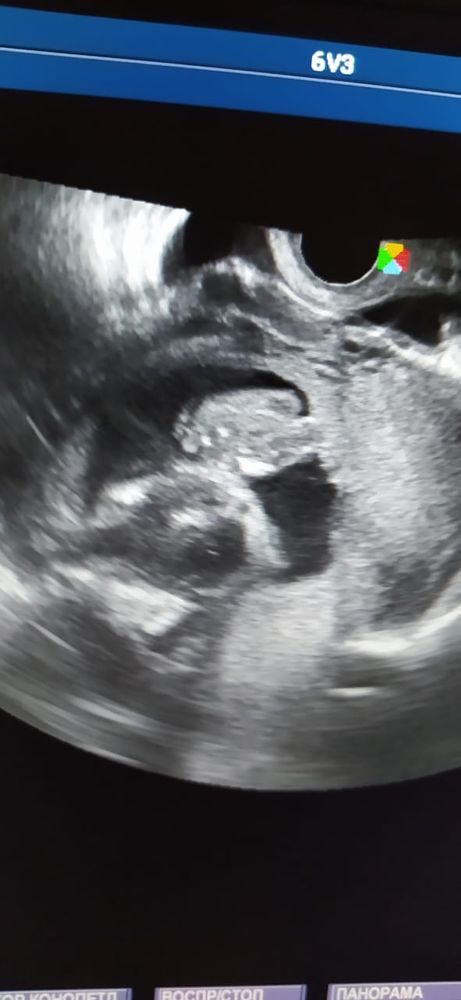

СЛАДКИЕ ПЯТОЧКИ МОЕГО СЫНОЧКА ❤❤❤

Лежу в гинекологии на сохранении))) укрепляют матку, у нас гипертонус и была не большая отслойка. Все у нас хорошо, капаем внутривенно магнезию, живот уже мягкий не каменеет и не кровит. Делали на днях УЗИ и мой малыш показал свои пяточки это так мило, что врач сама предложила сфоткать его пятки 🤤🥰 это редкость говорит когда пятками упирается на датчик ))) Оставлю тут на память.💫💙

Фото прилагаю.